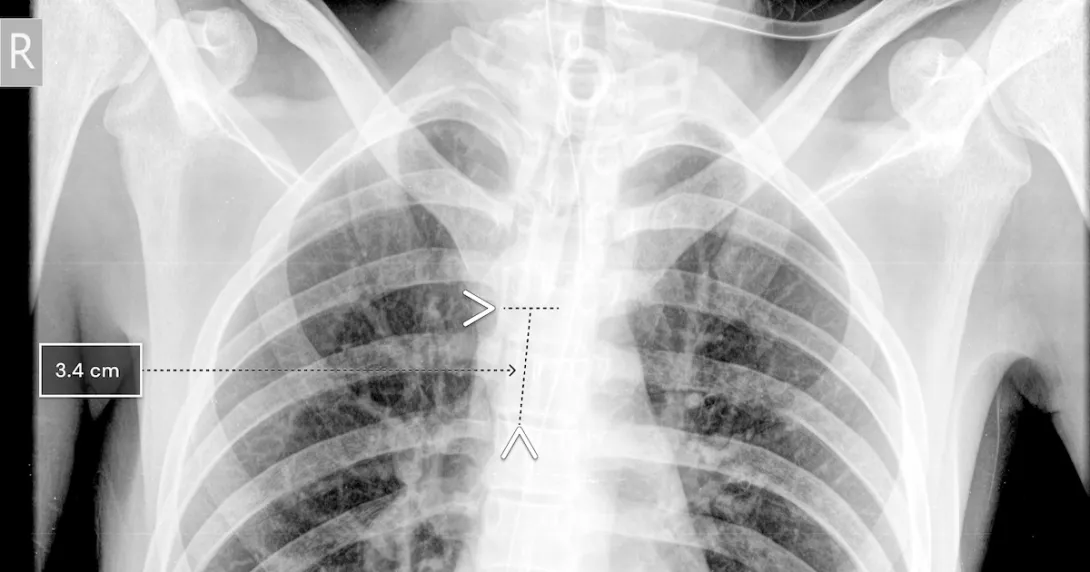

A chest x-ray showing Qure.ai's technology for breathing tube placement

Photo: Qure.ai

Using chest x-rays, the qXR-BT algorithm can analyze the position of the breathing tube. It automates measurement and can report accuracy to the clinician, who can then decide if the tube needs to be re-placed.